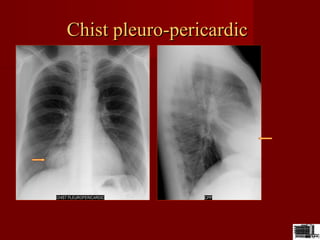

Chist pleuro-pericardicChist pleuro-pericardic

Formatiune cu sediul in mediastinul anterior etaj inferior ,unghiul

cardio-frenic omogena,contur net

•Chist pleuro-pericardicChist pleuro-pericardic

CT –chistul pleuro pericardic se

localizeaza cel mai frecvent in

unghiul cardiofrenic drept

este o structura chistica cu o

densitate de –5-25 UH

peretele este fin

dupa admininstrarea substantei

de contrast nu-si modifica

densitatea

Chist pericardicChist pericardic

•masa in unghiul

cardiofrenic anterior

•densitate lichidiana